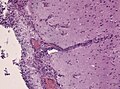

Brain abscess

At low magnification a cavity whithin brain tissue is evident (Picture 1). The necrotic core, filled with pus, consists mainly of neutrophils and macrophages. The abscess is surrounded by a fibrous capsule consisting of capillaries, macrophages, mononuclear cells, and reactive astrocytes (Picture 2). Collagen is produced by vascular cells and walls off the infection (Picture 3). Special stains (or molecular analyses) are needed to identify the causative agent.